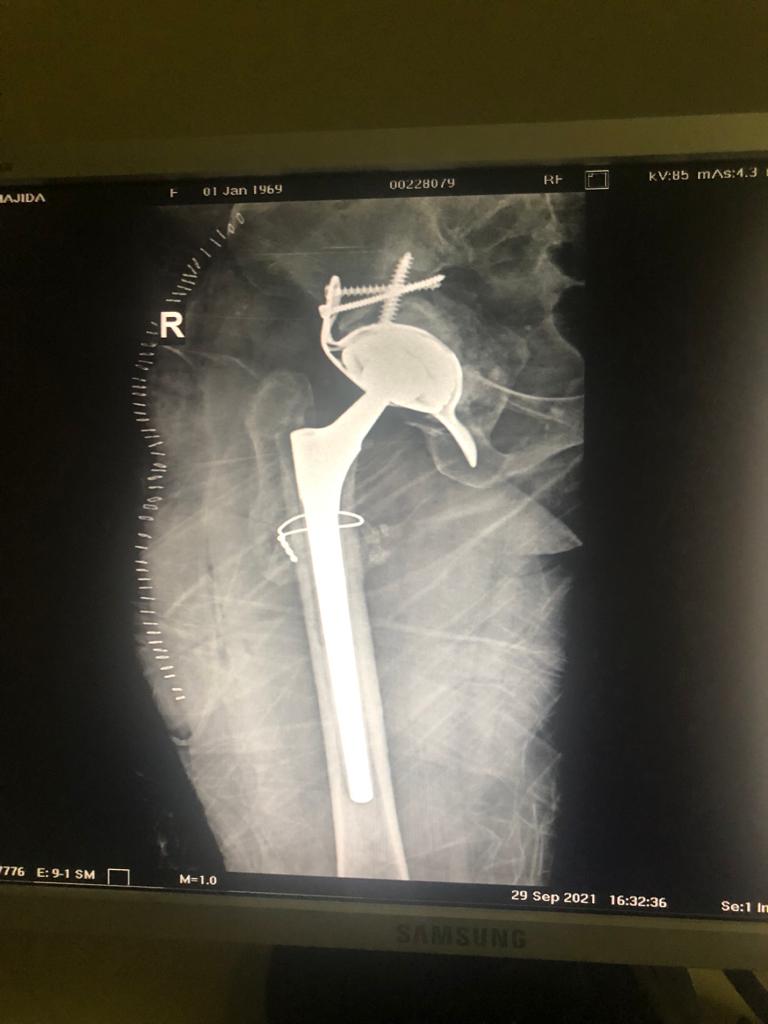

Revision Total Hip Arthroplasty